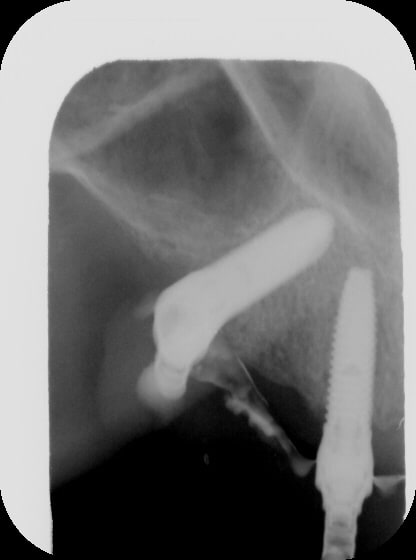

je vous montre le bas ;) oups!

(rrrhhh....les radio, dans ces secteurs là aplatissent tout, on dirait des implants presque parallèles... rrhhhh...)

Gin1 vfjd6v - Eugenol

Gin2 lzgl9h - Eugenol

Gin3 zmirus - Eugenol